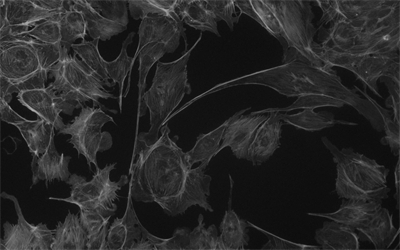

MHS700-MC(黑白)相機(jī)采用Sony Exmor CMOS芯片,針對傳感器固有的熱噪聲,專門設(shè)計了高效制冷模塊使得相機(jī)傳感器的工作溫度比環(huán)境溫度低達(dá)-40度,大大降低了圖像噪聲,保證了圖像質(zhì)量的獲取。

相機(jī)可用于弱光或熒光圖像的拍攝與分析,主要應(yīng)用于以下領(lǐng)域顯微拍攝:

• 明場顯微鏡;

• 暗場,微分干涉 (DIC) 顯微鏡;

• 活體細(xì)胞成像,細(xì)胞或組織病理學(xué)檢測,細(xì)胞學(xué);

• 缺陷分析,半導(dǎo)體檢測,精密測量;

• 微光熒光成像,GFP 或 RFP 分析,熒光原位雜交(FISH);

• 熒光共振能量轉(zhuǎn)移顯微鏡,全內(nèi)反射熒光顯微鏡,實時共聚焦顯微鏡,失效性分析,天體照相。